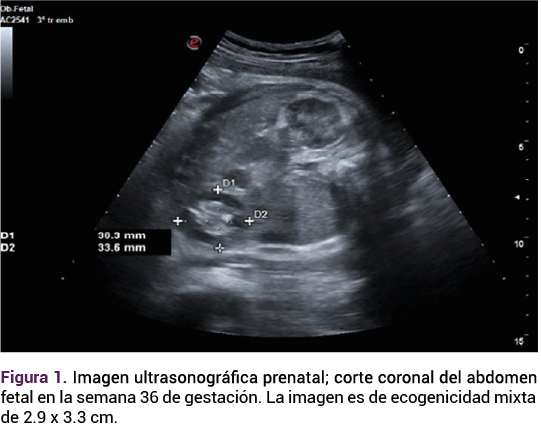

El ultrasonido obstétrico reportó: feto único, vivo, con frecuencia cardiaca de 135 lpm, peso estimado de 2767 g en el percentil 71, placenta fúndica grado II de Granum y líquido amniótico cualitativamente normal. Los genitales se advirtieron fenotípicamente masculinos, sin evidenciar el testículo derecho en la bolsa escrotal. La imagen ecogénica era mixta respecto de la ecogenicidad de los tejidos circundantes de 29 x 23 mm de una tumoración móvil adyacente al colon, cercana a la pared abdominal. La aplicación de Doppler color fue negativa, sin efecto de masa hacia otras estructuras abdominales, sin líquido libre o gas. El resto de la exploración transcurrió sin alteraciones. Figuras 1 y 2.

<strong>Figura 1</strong>

Figura 1.

Ante las características ecográficas de la tumoración se decidió la conducta expectante, con seguimiento ecográfico. A las 37 semanas el feto continuaba con una frecuencia cardiaca de 140 lpm, peso de 3186 g, percentil 84, placenta fúndica, líquido amniótico cualitativamente normal. Sin embargo, con un aumento notable del tamaño de la tumoración intraabdominal, ahora 1 cm más grande, respecto del rastreo previo.